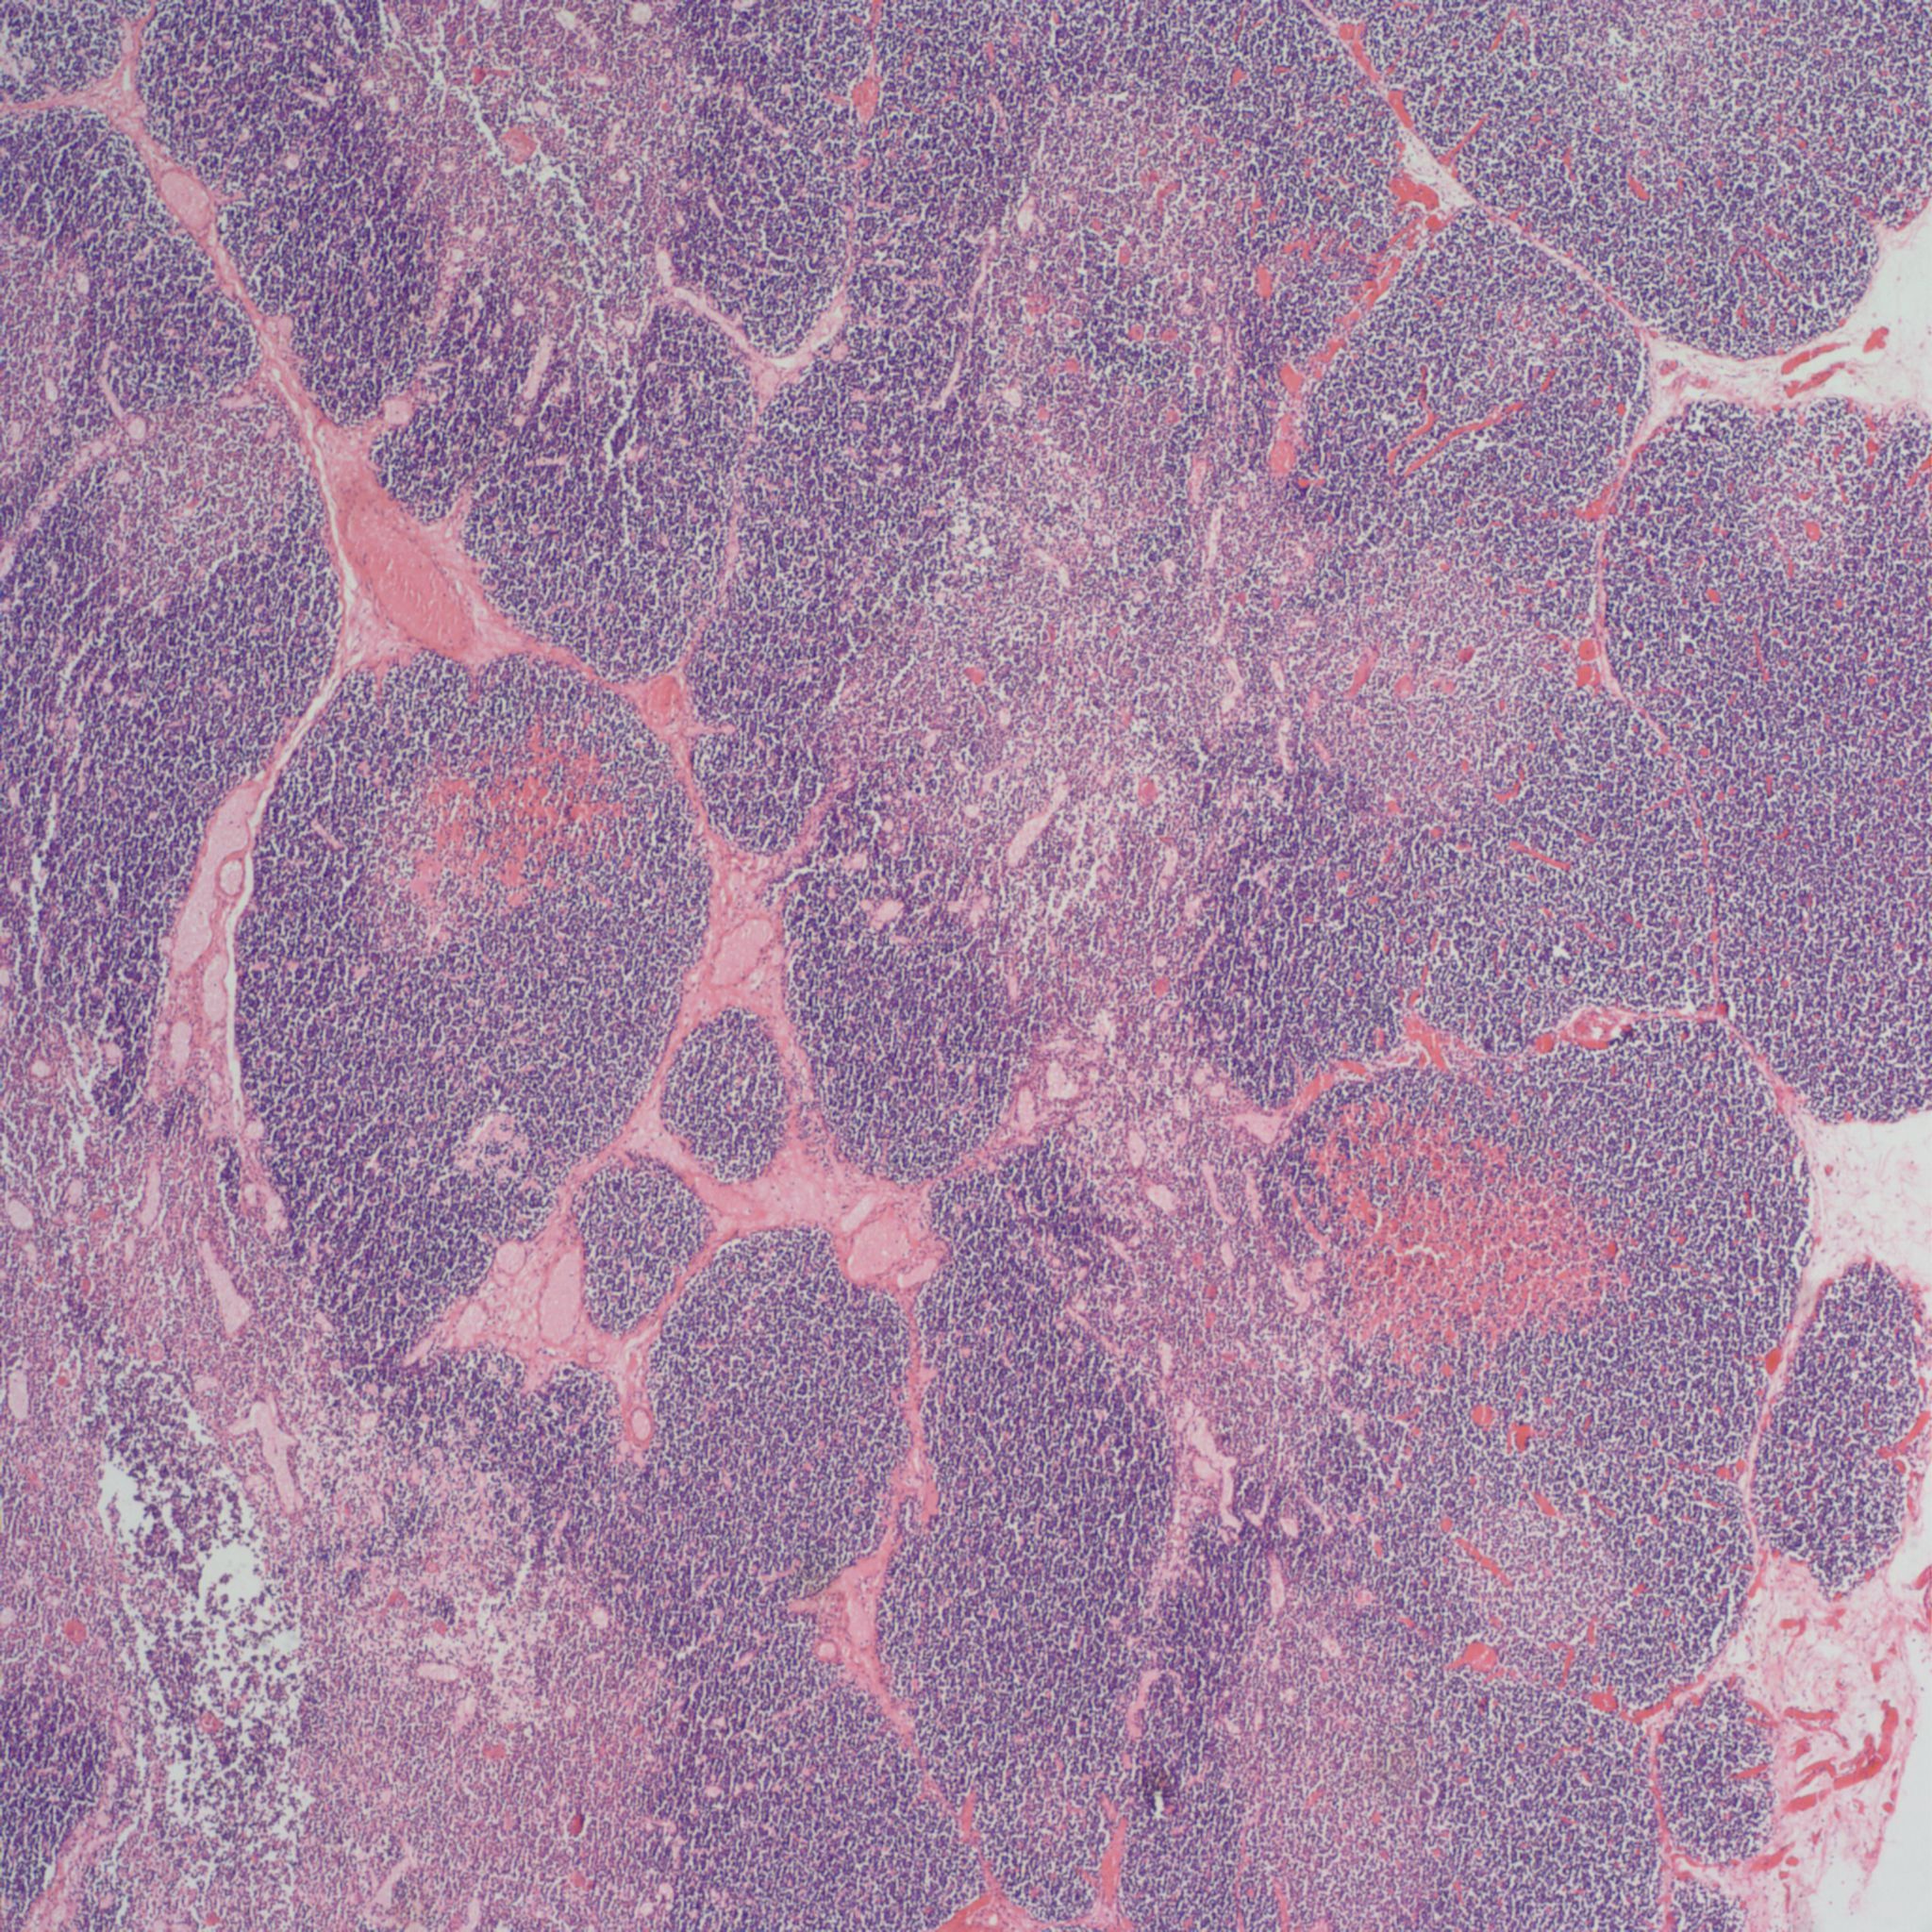

As involution progresses, there will be a progressive loss of cortical lymphocytes. The cortex will appear notably thinned compared to the medulla with thinner lobules and more connective tissue between lobules (Figs 11a, 11b, 12a, 12b, 13a, 13b).

A staging system has been proposed for this progression: stage 0 = no histopathologic changes, stage 2 = starry sky appearance, stage 3 = loss of distinction of the medulla and cortex, and stage 4 = loss of all cortical lymphocytes with an inverted appearance[16]. Based on the clinical histories, the stage has been correlated with duration of involution as follows: stage 0 = 0-12 hours, stage 1 = 12-24 hours, stage 2 24-48 hours, and stage 4 > 72 hours. A continuous stress keeps the thymus involuted, and results in decreased weight as demonstrated in human autopsy and in experimentally in the monkey with repetitive dexamethasone injections [17].The thymic to brain weight usually reflects the histological degree of involution when the small size is due to histological identified involution and not a failure of thymic development.

The complexity of thymic changes is demonstrated in a case of a 22 week gestation infant with a week of preterm premature rupture of membranes who was treated with betamethasone (a synthetic corticosteroid that can cross the placenta to the infant and used to promote lung maturation) and antibiotics. The infant survived for three quarters of an hour. The placenta demonstrated choroamnionitis with some fetal inflammation in the superficial chorionic vessels. The autopsy demonstrated complete involution of the thymus, follicular formation in the spleen, and extensive, intense acute pneumonitis with no growth of microorganisms on lung culture. The thymus demonstrated an inverted picture with no cortex and small lymphocytes in the medulla. The cortical rim demonstrated a compact epithelial layer. (Figs 16, 17) This infant had evidence of acute inflammation, and antibody stimulation, making it impossible to assess the changes due to the exogenous steroid.